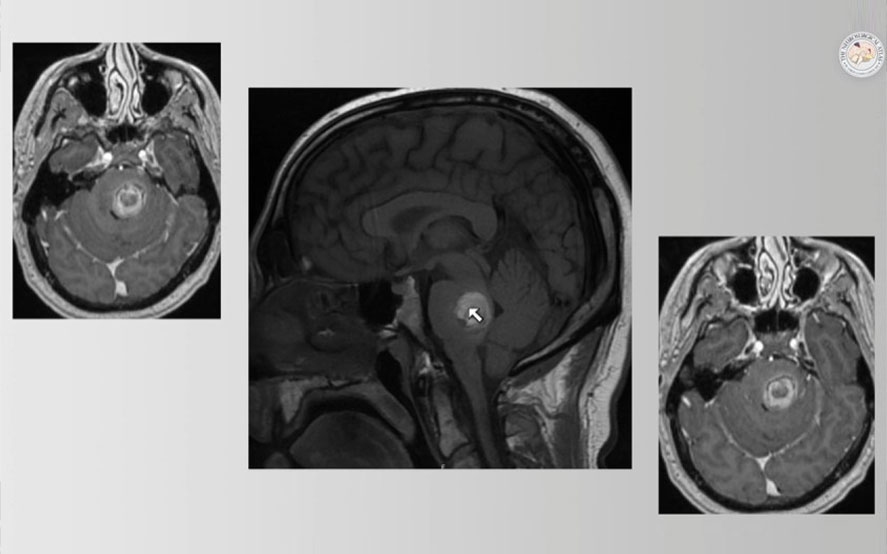

•  Cavernous Malformation

We specialize in the most challenging and symptomatic cavernoma cases:

•  Cavernomas causing recurrent hemorrhage

•  Cavernomas causing drug-resistant seizures

•  Brainstem cavernomas (high-risk locations)

•  Spinal cord cavernomas

•  Cavernomas in eloquent brain regions